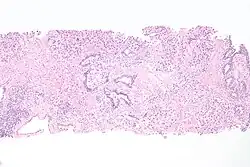

Microanatomy

The cells lining the urethra (the epithelium) start off as transitional cells as it exits the bladder, which are variable layers of flat to cuboidal cells that change shape depending on whether they are compressed by the contents of the urethra.[16] Further along the urethra there are pseudostratified columnar and stratified columnar epithelia.[16] The lining becomes multiple layers of flat cells near the end of the urethra, which is the same as the external skin around it.[16]

There are small mucus-secreting urethral glands, as well as bulbo-urethral glands of Cowper, that secrete mucous acting to lubricate the urethra.[16]

The urethra consists of three coats: muscular, erectile, and mucous, the muscular layer being a continuation of that of the bladder.